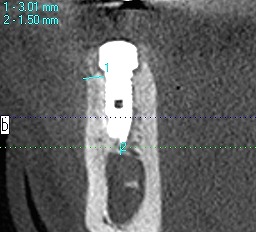

埋入後を見ていただくと距離もないことがわかります

10mmのインプラントでもギリギリのところかと思います

埋入後のCTになります

動脈性の出血もなく神経には障害がありませんが、

距離がないことがわかります

わずか1mm、2mmの世界の勝負なためいつもいい緊張感

にて行っています